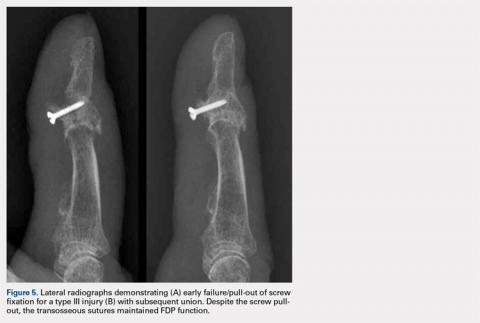

Transosseous tendon repair is a cost-effective option that obviates many complications commonly observed with other fixation methods. By keeping the suture within the body, the complications inherent in external sutures and buttons are eliminated, including the loss of fixation as a result of button or suture damage and facilitating hand hygiene maintenance. The rate of infection is also reduced. Moreover, the risk of nail deformities is decreased because the suture is not passed through the nail bed and nail plate in the described technique. Occasionally, some patients do note irritation from the dorsal suture knot under the thin skin proximal to the germinal matrix. This can be easily addressed in the clinic by removing the knot under local anesthesia following sufficient tendon healing. Additionally, the described technique can be used safely in pediatric patients with open physes because the needles can be placed to prevent violating the physis. This technique can be performed in conjunction with the skeletal fixation of type III, IV, and V jersey fingers. In our experience, the transosseous suture repair is more secure than the limited screw fixation, which can be accomplished in many type III jersey fingers, and in at least 1 case, has maintained flexor function when the skeletal fixation of the jersey finger has failed (Figures 5A, 5B).